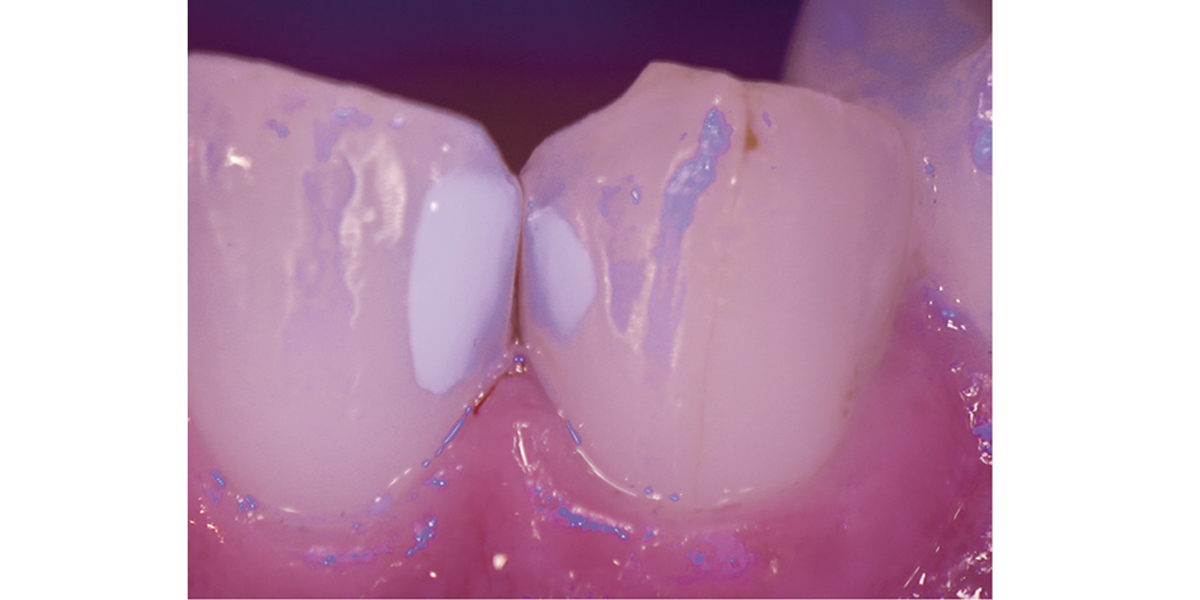

観察しやすくなるブルーライト機能

観察がしやすくなるブルーライト機能

ブルーライトでレジン充填部などの状態を観察しやすい映像が得られます。直視では認識しづら い余剰セメントまで把握でき、より精細な治療をサポートします。